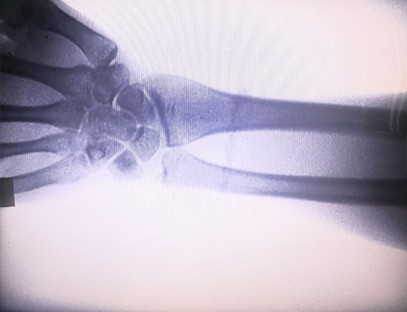

Especialização:Projetado para as necessidades de clínicas ortopédicas, particularmente adequado paraImagem de raio-Xde membros como mãos, pulsos, cotovelos, ombros, joelhos, tornozelos, etc.

Imagem nítida:Tecnologia avançada de imagem digital é usada para fornecer imagens de raios X de alta qualidade, ajudando os médicos a diagnosticar a condição com precisão.